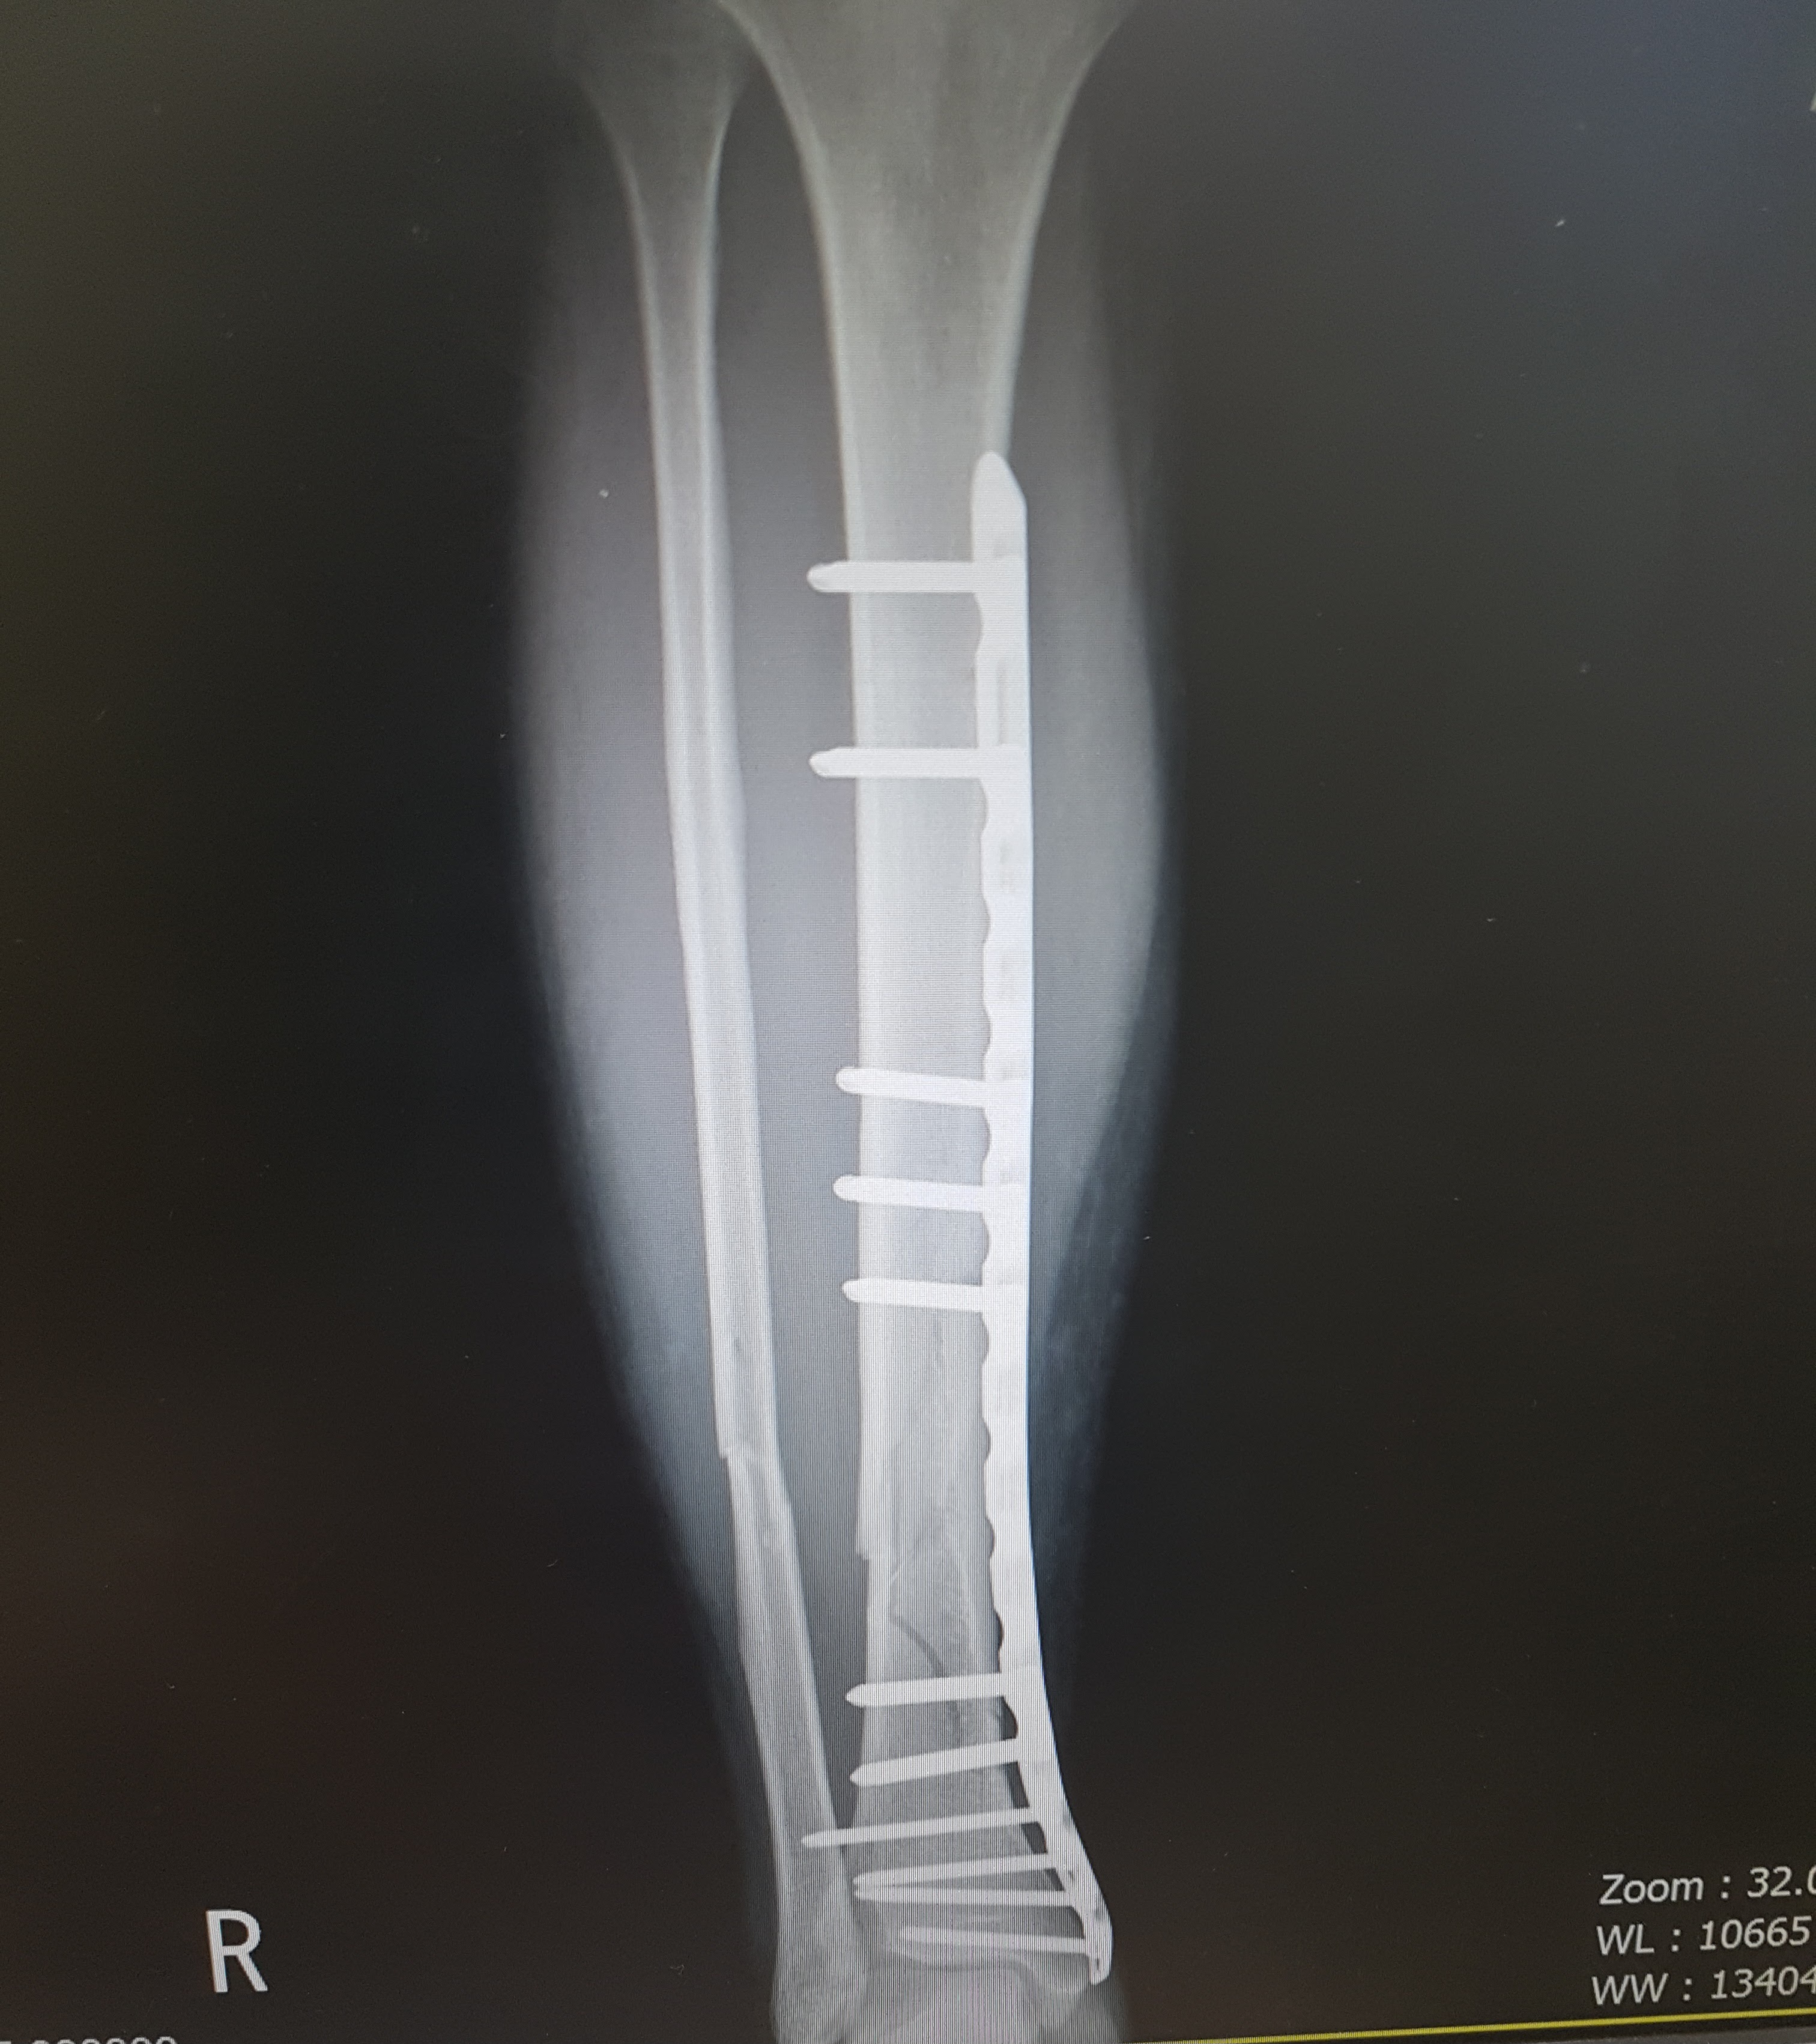

[유머] 멀쩡한 길걷다 발목에 금가는 애 봄 ㅋㅋㅋㅋㅋ [67]

다행히 엑스레이랑 초음파했는데 인대나 다른 건 괜찮데. 멀쩡히 붙으면 핀 안박아도 된데서 다행임 ㅠ | 25.03.26 16:17 | | |

그나마 다행이네요. 뼈보단 연부조직이 회복되어도 기능이 안돌아올 가능성이 있어서 위험한데 뼈만 다치셨다니 회복 잘만되시면 운동능력은 대부분 회복되실 가능성 높겠네요 | 25.03.26 16:22 | | |